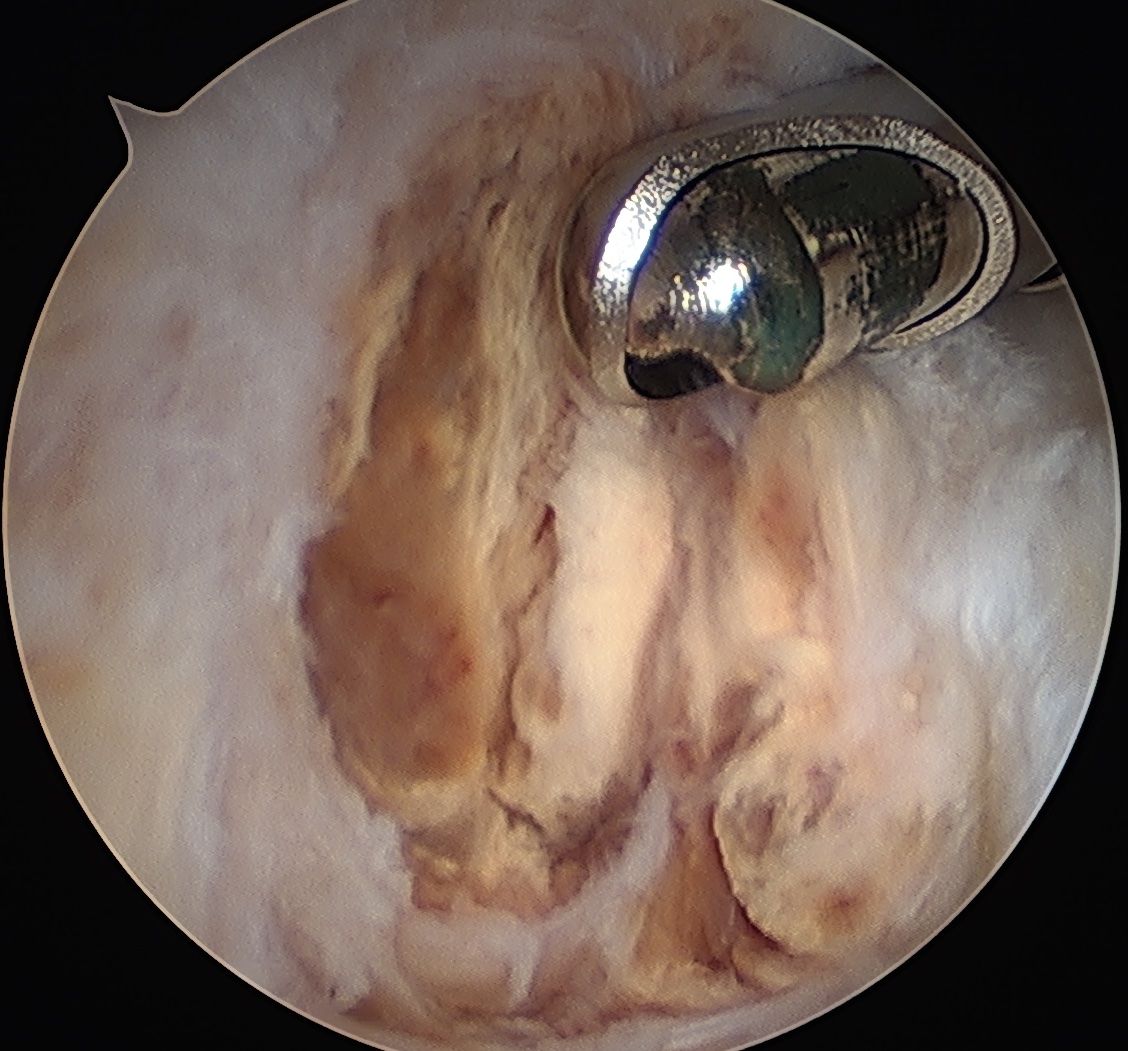

Pathology

Histology

Hemosiderin stained multinucleated giant cells

Arthroscopy

Diffuse knee joint